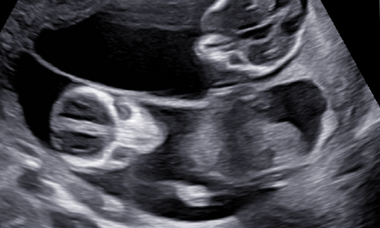

Join us for this engaging and informative course. Together with a panel of expert speakers from around the world, they will dive into the most challenging and evolving aspects of first trimester fetal imaging. This course offers attendees a valuable opportunity to gain a comprehensive understanding of the new advances in this area and learn how to apply them in practical situations.

• Focusing on the rare and uncommon anomalies pertaining to first trimester

• Current concepts in screening and ultrasonography in first trimester

• Recognizing uncommon fetal anomalies